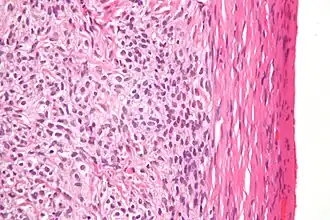

Fort grossissement d'un thécome, coloration à l'hématoxyline et à l'éosine.

Les thécomes ou tumeurs des cellules thèques sont des néoplasmes ovariens bénins composés uniquement de cellules thèques. Histogénétiquement, ils sont classés comme des tumeurs du cordon sexuel et du stroma.

Grossièrement, la tumeur est solide et jaune.

Au microscope, les cellules tumorales ont un cytoplasme abondant rempli de lipides.